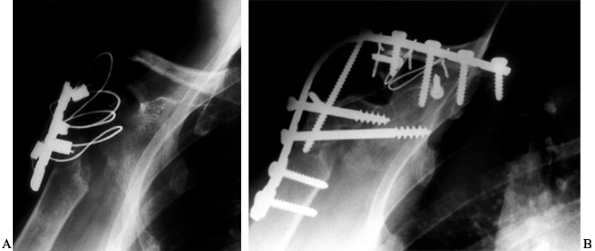

In many circumstances in which an arthrodesis is necessary, significant scapular and proximal humeral osteopenia has occurred (Fig. 103.11A).

Screw purchase in the scapular spine can be poor. The strength of the

fixation can be improved by placing cerclage wires around the pelvic

reconstruction plate and the base of the acromion (Fig. 103.11B).

Figure 103.11. A:

Radiographs of a patient who had a previously failed hemiarthroplasty

and hypoplastic glenoid. Because there was bone loss on the humerus and

a hypoplastic glenoid, she went on to nonunion after an unsuccessful

attempt at arthrodesis. B: Revision

glenohumeral arthrodesis was performed using plate fixation and local

vascularized bone graft. Note that plate fixation to the spine of the

scapula was augmented with three cerclage wires.